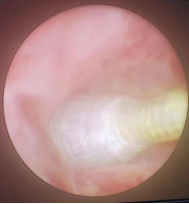

考虑患儿肝移植手术腹腔粘连紧密及局部解剖位置改变,开腹手术难度较大。多学科团队多次进行会诊讨论,最后决定先行经皮肝穿刺胆道引流(PTCD)减轻炎症及黄疸,术中同时取肝脏活检进一步明确诊断。患儿术后胆汁引流通畅,肝功恢复正常。待原吻合口炎症水肿消退及经皮穿刺隧道稳定后,患儿于6月1日在全麻下行胆道镜取石,取石完成后术中胆道造影可见造影剂通过胆肠吻合口,继续放置T管引流,1个月后经T管造影提示肝内外胆管通畅,造影剂可进入肠腔。随后,患儿于8月11日在全麻下行经皮胆道镜检查,经原PTCD皮肤窦道置入胆管镜,在胆道镜直视下导丝引导置入4mm球囊扩张器反复扩张原胆肠吻合口(图2-4),扩张完成后胆道镜可轻松通过胆肠吻合口进入空肠,造影显示吻合口通畅(图5),放置适当直径引流管支撑引流,术后患儿无特殊不适。

图4:扩张期予以扩张,每次放置扩张器约5分钟